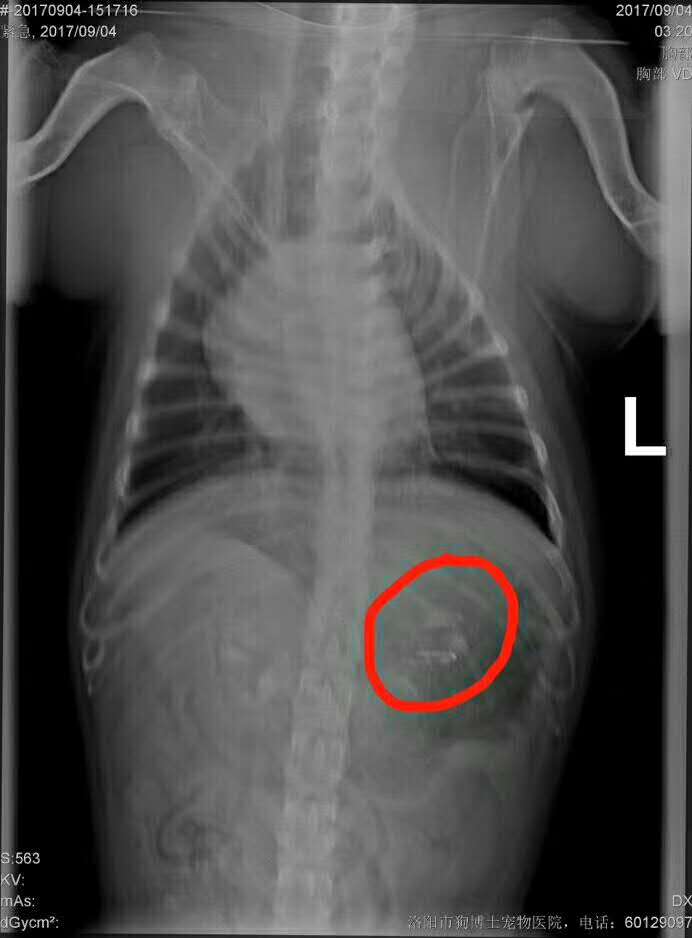

胃內(nèi)異物取出術(shù):      斗牛,牛牛,帥哥,今天下午陪主人釣魚,不慎將魚鉤吞入胃內(nèi) 來醫(yī)院手術(shù)取出,手術(shù)順利完成,現(xiàn)已蘇醒